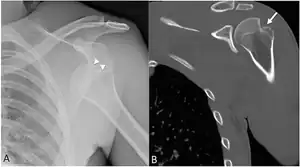

| Anterior shoulder dislocation on X-ray with a large Hill–Sachs lesion | |

X-ray at left shows anterior dislocation in a young man after trying to get up from his bed. X-ray at right shows same shoulder after reduction and internal rotation, revealing both a Bankart lesion and a Hill-Sachs lesion.